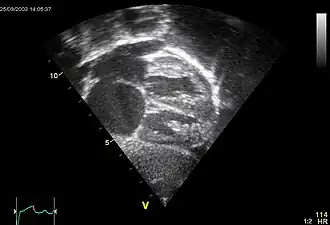

Comunicación interauricular

La comunicación interauricular (CIA) es una cardiopatía de origen congénito acianógena (sin cianosis), consistente en una deficiencia del septum o tabique que separa las cavidades del corazón denominadas aurículas y que resulta en una libre comunicación entre el lado derecho e izquierdo de las aurículas. Puede estar situada en cualquier parte del mismo, siendo su localización más frecuente en la región de la fosa oval y así se denomina tipo ostium secundum.